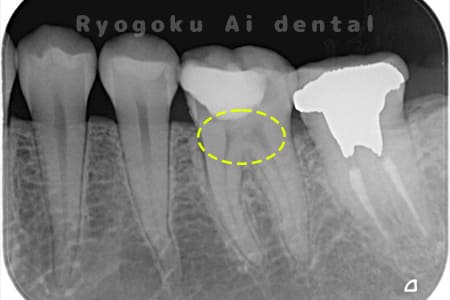

Case04

-

- 原因

- C3、重度カリエス

- 治療内容

- 17・15断髄治療

- 治療費用

- 154,000円

他院で神経をとるほどの虫歯があり、神経を残したいとのことで来院された患者様です。歯の神経を一部分取る断髄治療を行い、問題なく経過を追っています。

<リスク・副作用>

術後は痛み、腫れ、痺れなどの副作用が生じる場合があります。症状が再発する可能性があります。その場合は抜髄する必要があります。